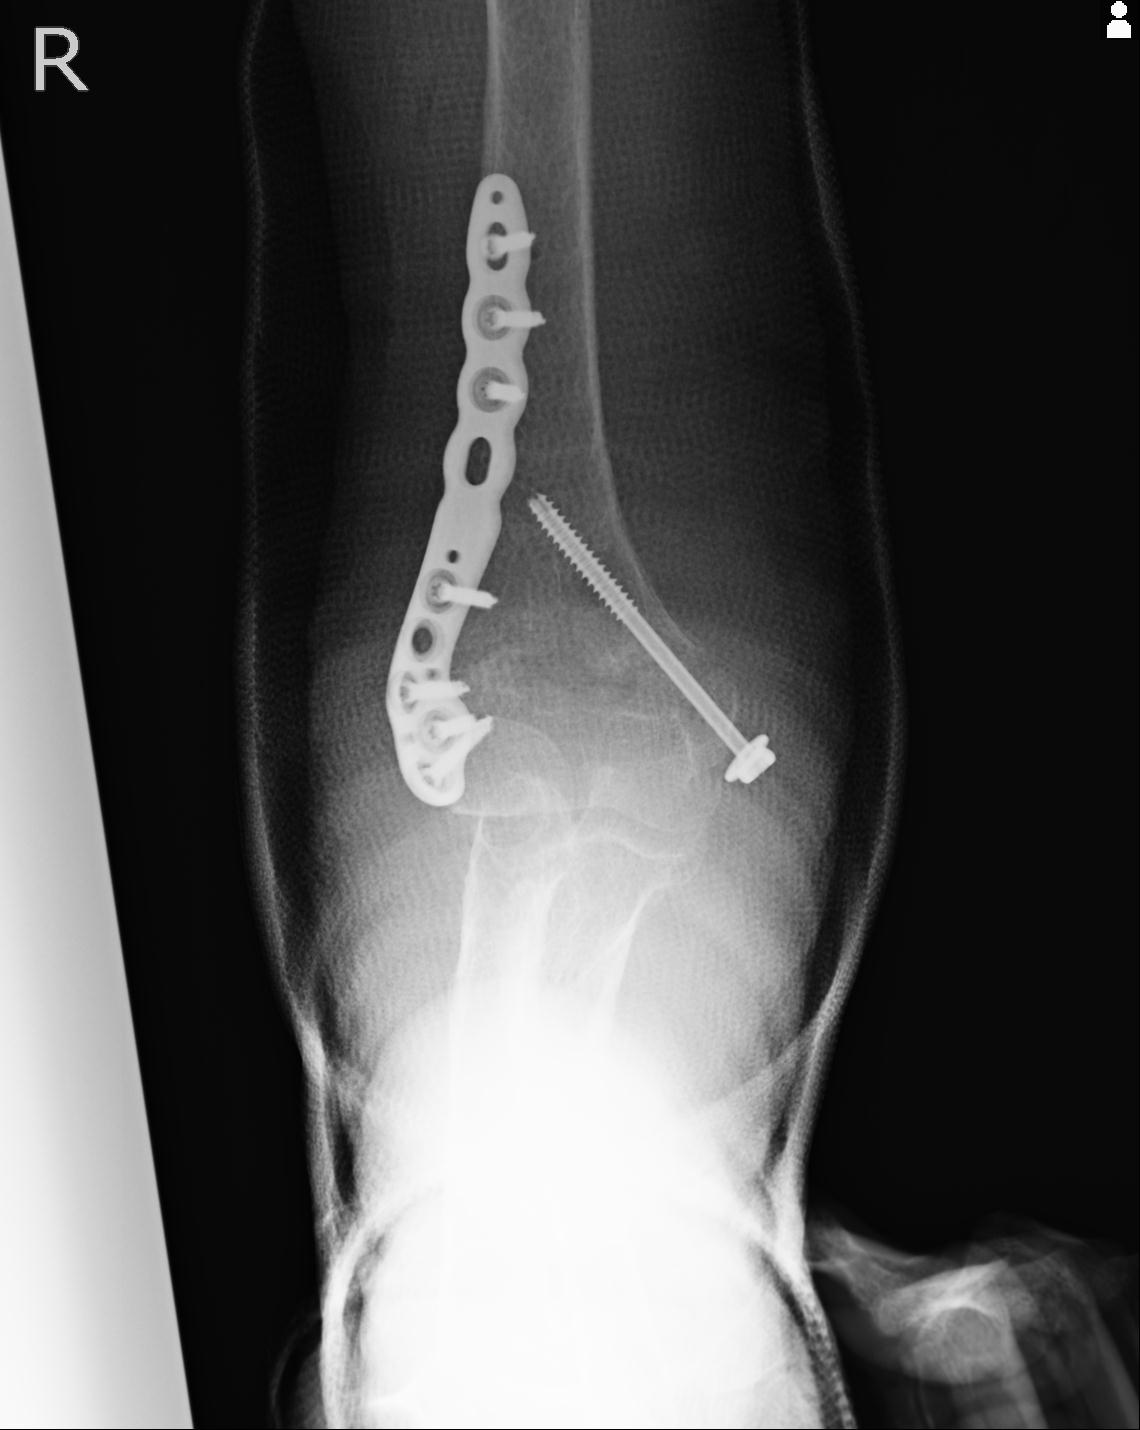

56476 8/28 4R 1/21 2R 左足関節 デジカメ写真 72歳女性 右足関節AS